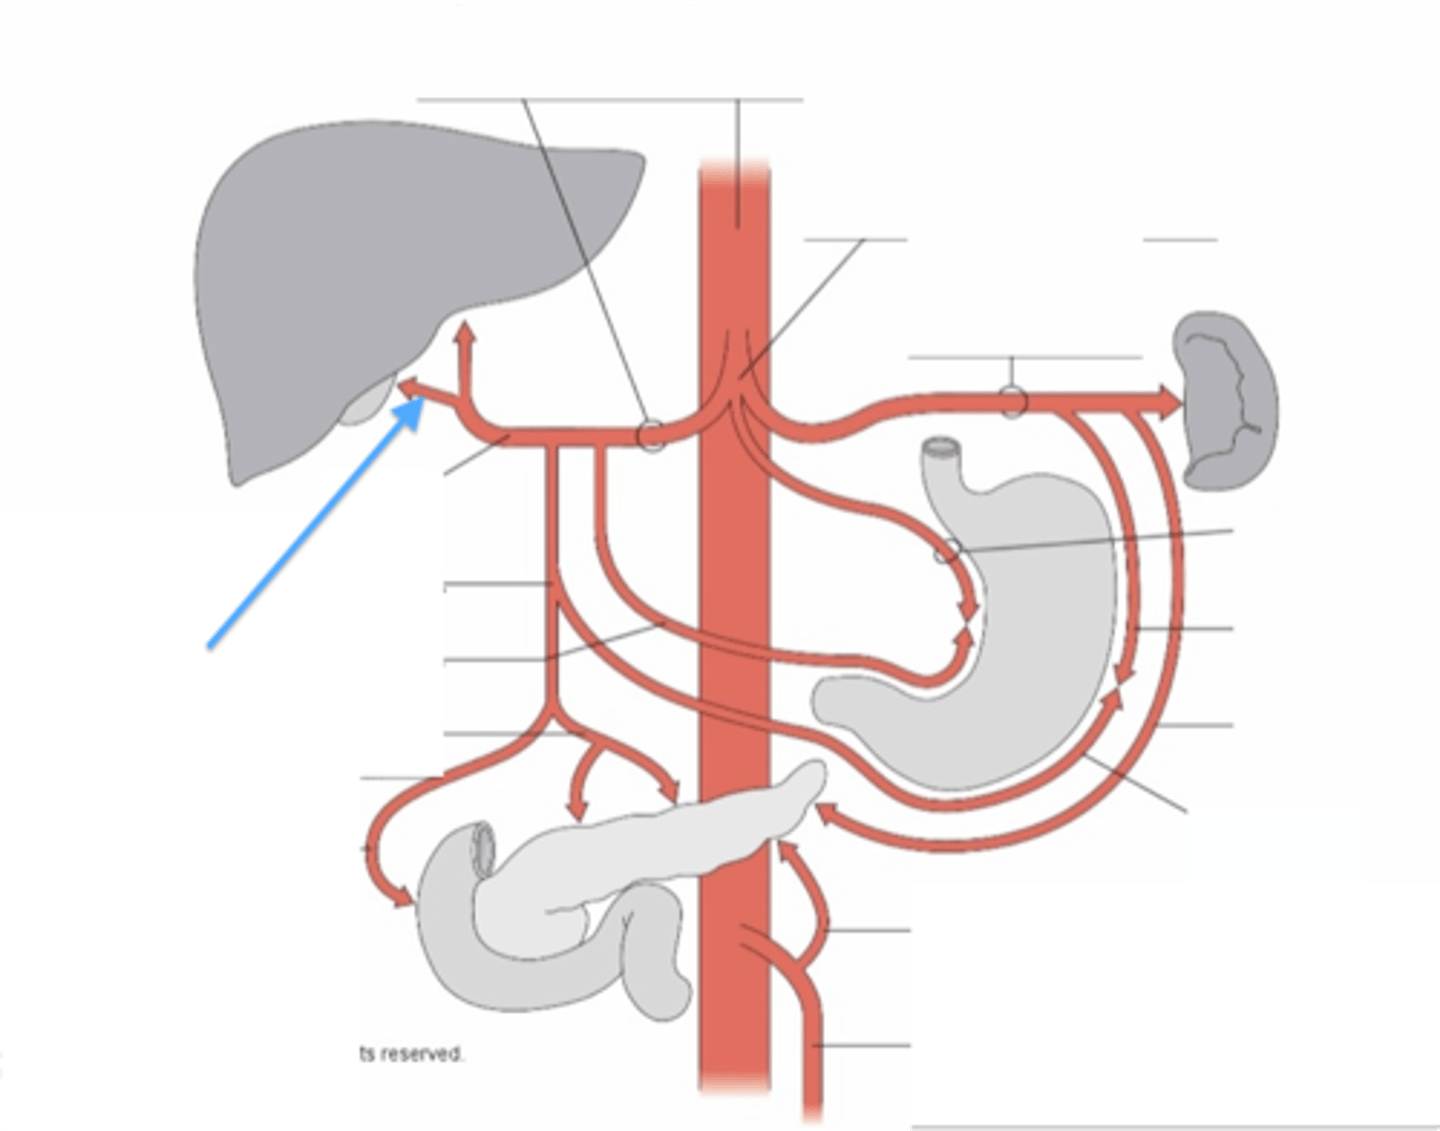

celiac trunk

left gastric artery

splenic artery

common hepatic artery

hepatic artery proper

gastroduodenal artery

superior mesenteric artery

inferior mesenteric artery